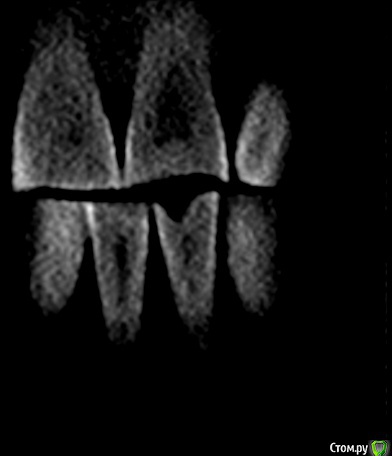

shurkne Опубликовано 10 мая, 2015 Поделиться Опубликовано 10 мая, 2015 (изменено) Здравствуйте!Зуб 1.3..есть небольшое углубление видимо вызванное стиранием.Выпил чая горячего,зуб легонько заныл в месте стирания и продолжает легонько поднывать.Подскажите что с зубом? и сколько там каналов?) Изменено 10 мая, 2015 пользователем shurkne Ссылка на комментарий

Гарриевич Опубликовано 10 мая, 2015 Поделиться Опубликовано 10 мая, 2015 Канала дваНадо холодом проверить зуб Ссылка на комментарий

shurkne Опубликовано 12 мая, 2015 Автор Поделиться Опубликовано 12 мая, 2015 (изменено) Четко 3.1 поднывает.(в первом сообщении ощибся с нумерацией)......выпил чая горячего и заныл немного....больше на температурные раздражители не реагирует никак....щас периодически немного беспокоит само место стирания Изменено 12 мая, 2015 пользователем shurkne Ссылка на комментарий